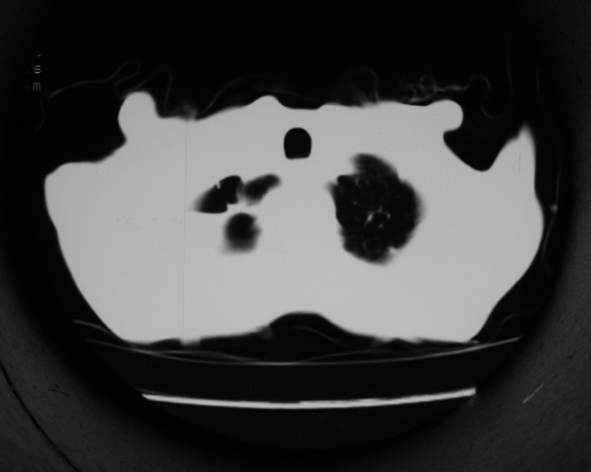

男53岁,咳嗽气短,以往身体健康.

右肺上叶多发多形态空洞及增殖灶,可见团块钙化,胸膜肥厚、粘连,考虑继发型肺结核可能性大

1.右肺上叶干酪性肺炎,2。肺气肿,肺大泡

右肺上中叶结核干酪性肺炎

右肺中上叶干酪性肺炎。

支持右上肺继发性肺结核并干酪性肺炎,右肺大泡,左肺代偿性气肿。